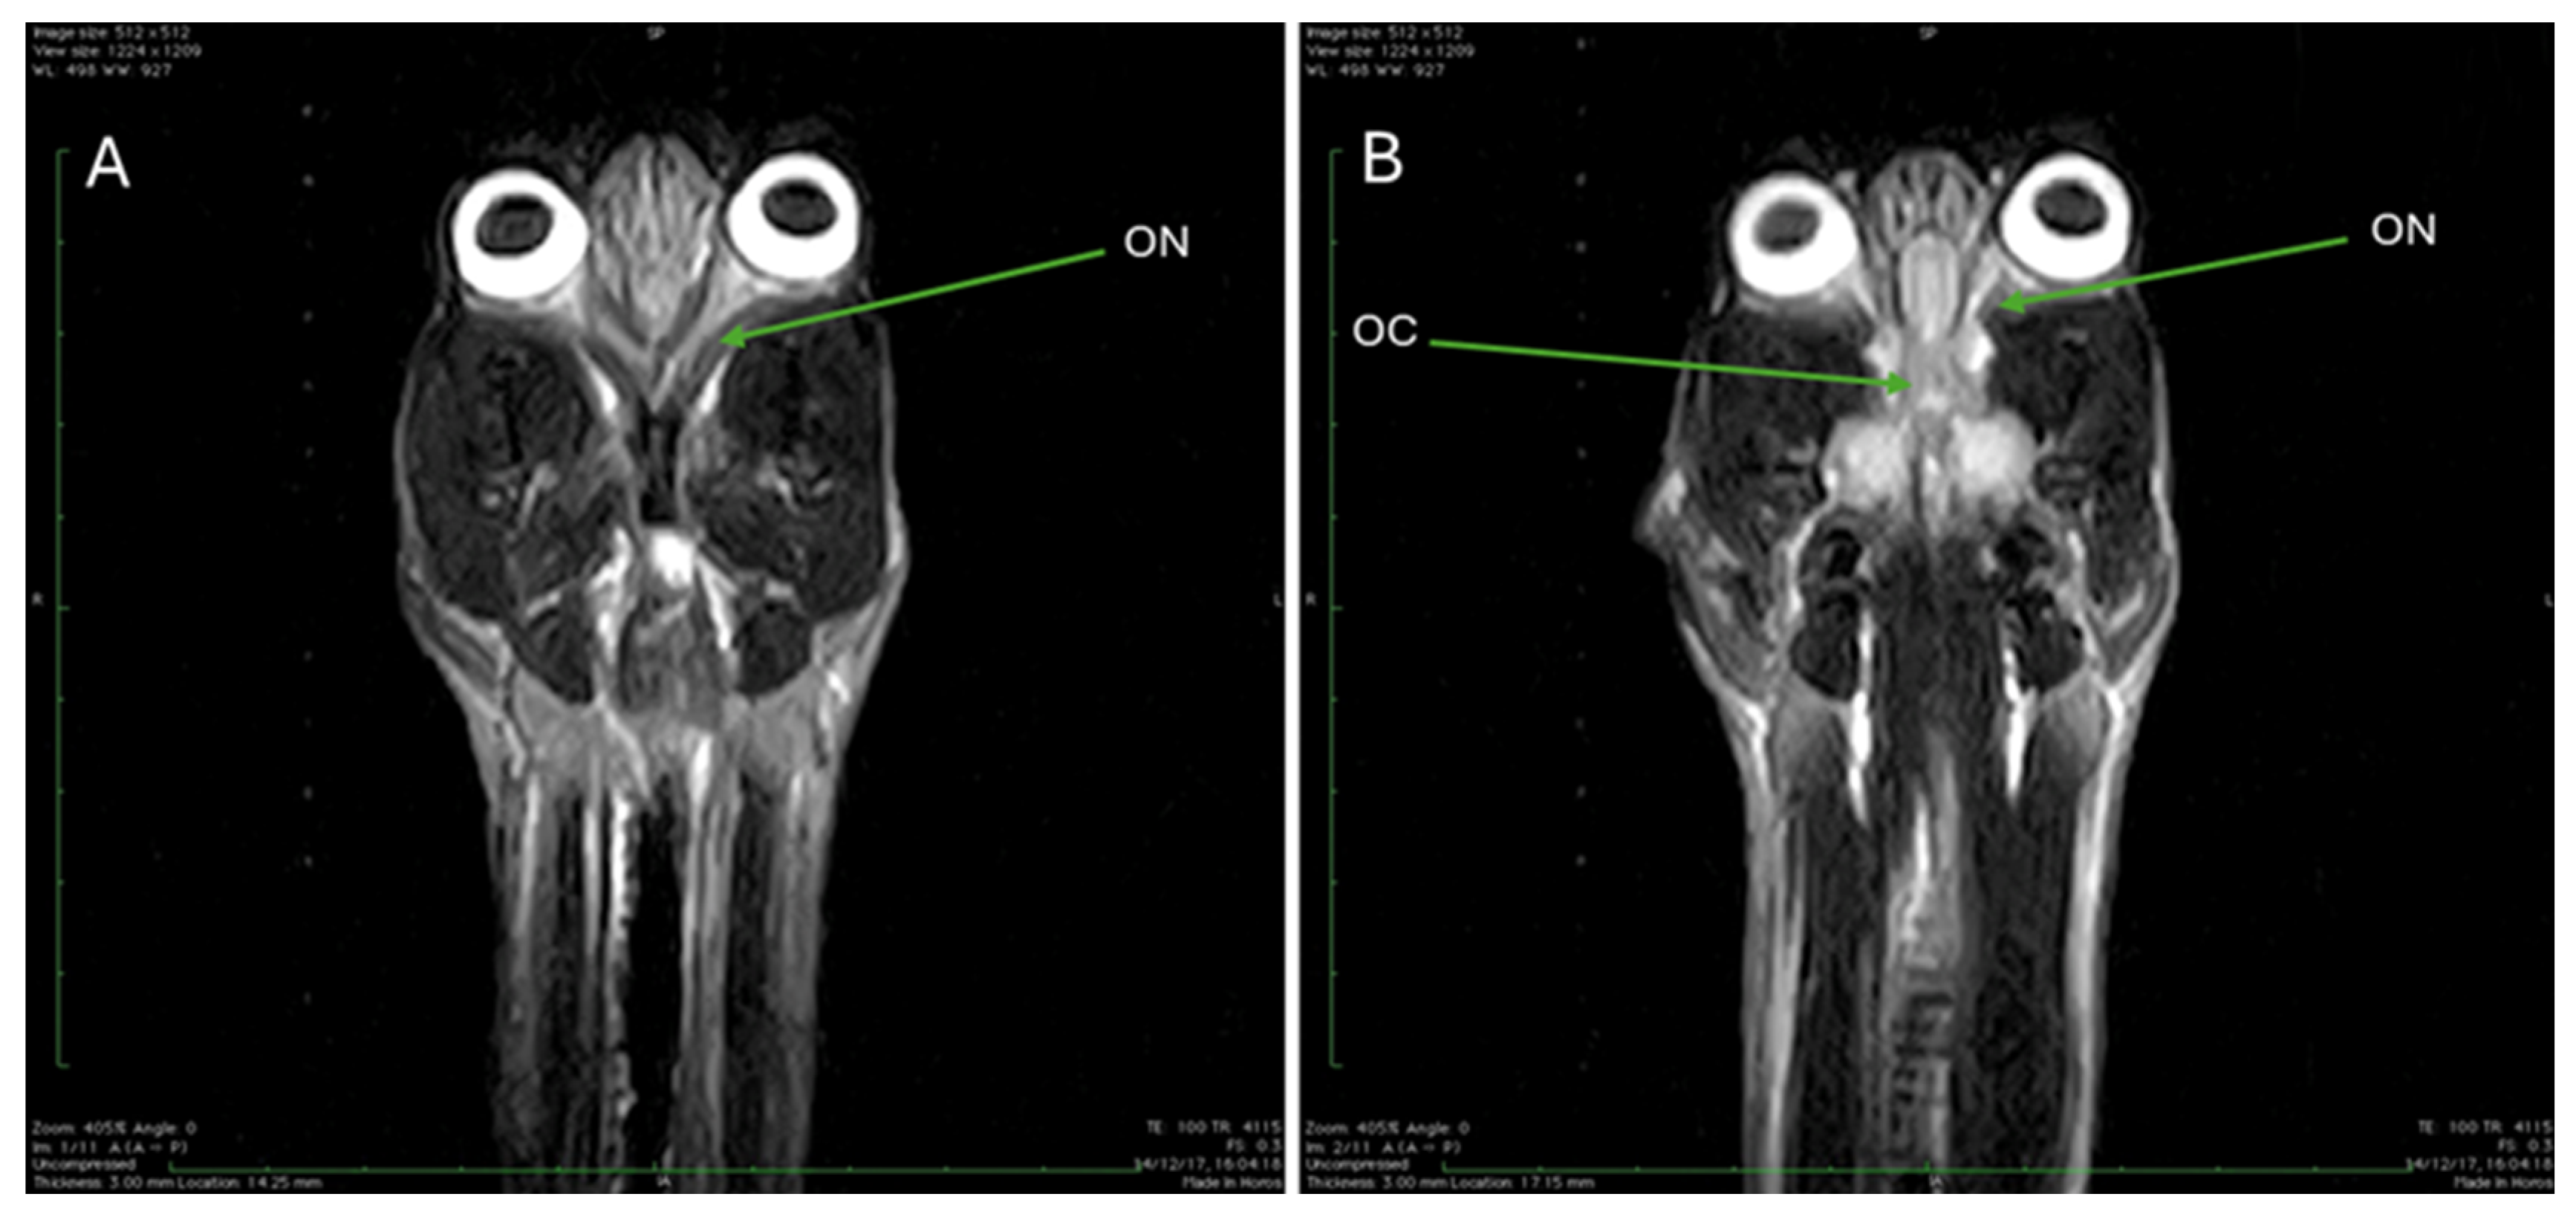

| ON | Optic nerve |

| OC | Optic chiasm |